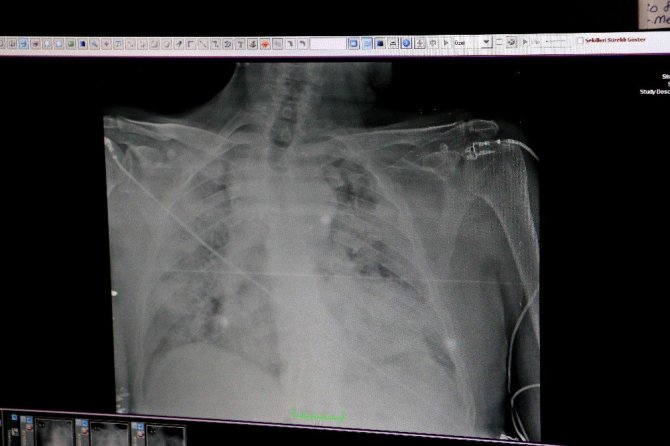

Tüm dünyayı etkisi alan ve ölümlere sebep olan korona virüs en çok akciğerleri etkiliyor. Akciğerlerde tutuluma yol açarak, solunum yetmezliği, nefes darlığı ve zatürreye sebep olan virüsün organa verdiği hasar, hastalığın yol açabileceği zararları gözler önüne seriyor. İhlas Haber Ajansı (İHA), Çukurova Üniversitesi Tıp Fakültesi Balcalı Hastanesi’nde Covid-19 tedavisi gören hastalara ait akciğer görüntülerine ulaştı. Görüntülerde, hastalığın ne kadar hızlı ilerlediği görülüyor.

Çukurova Üniversitesi Tıp Fakültesi Hastanesi Göğüs Hastalıkları Ana Bilim Dalı Öğretim Üyesi ve Başhekim Yardımcısı Doç. Dr. Ezgi Özyılmaz, röntgenleri incelediği sırada normal sağlıklı bir akciğerde röntgen üzerinde siyah alanların olması gerektiğini ancak korona virüs hastalarının akciğerlerinin tamamen beyaz göründüğünü ve solunum güçlüğünü çekip makineye bağlı yaşadıklarını söyledi.

Korona virüsün akciğere indiği hastaların röntgen sonuçlarının kötü olduğunu belirten Özyılmaz, “Aslında teorik olarak daha önce gördüğümüz diğer mikroplara ve diğer nedenlere bağlı şeylere benziyor. Ancak bir takım nüans farklı var. Biz artık akciğer grafisinde görür görmez bunun korona virüs olup olmadığını hemen anlıyoruz” ifadelerini kullandı.